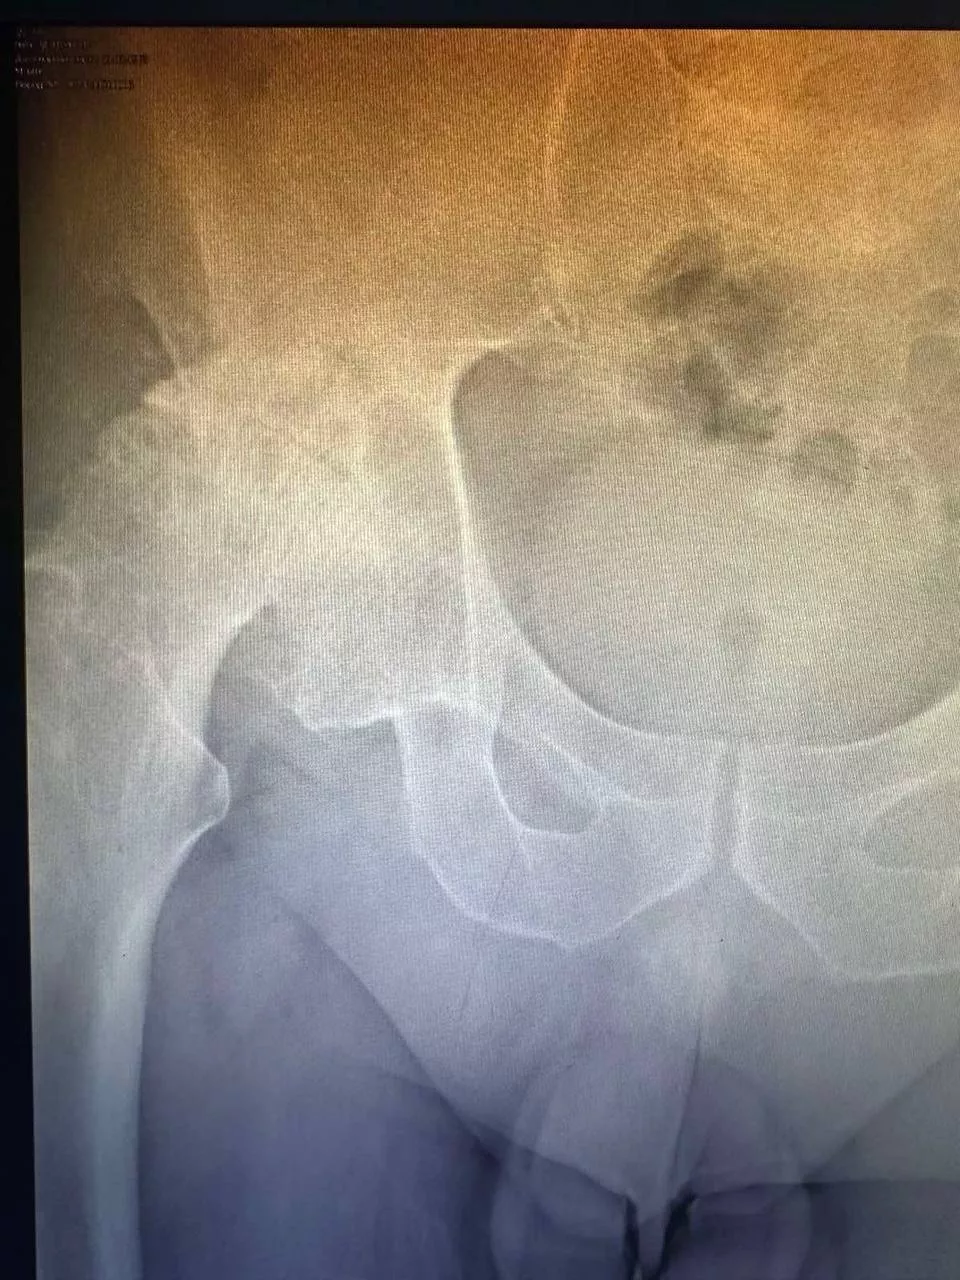

Ендопротезування кульшового суглоба

Заміна кульшового суглоба — одна з найефективніших операцій, яка вважається "золотим стандартом" в ортопедії. Цей вид хірургічного втручання виконується для лікування важких захворювань суглобів і відновлення їхньої рухливості. Під час операції пошкоджений суглоб замінюється на штучний імплантат, що дає змогу значно зменшити біль і повернути свободу рухів. Ендопротезування допомагає відновити повноцінне функціонування кульшового суглоба, забезпечуючи пацієнту активне і комфортне життя.